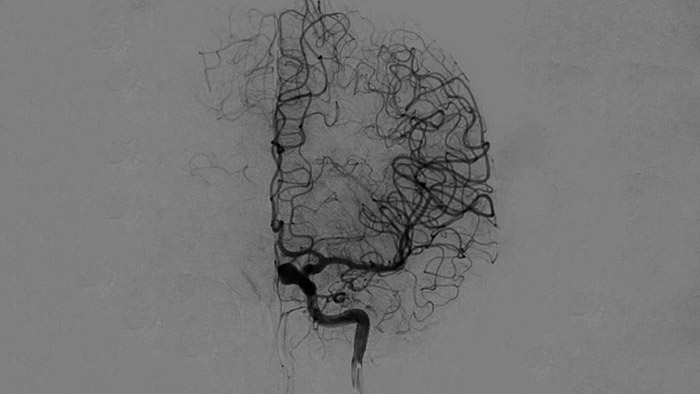

Подтверждение успеха лечения

Визуализация DSA

Высококачественная визуализация в режиме DSA позволяет оценить, был ли тромб полностью удален и произошло ли растворение сгустков крови в головном мозге. Врачам предоставляется возможность проверить восстановление кровотока в области ишемической полутени, а также наличие кровотечений в периоперационный период.